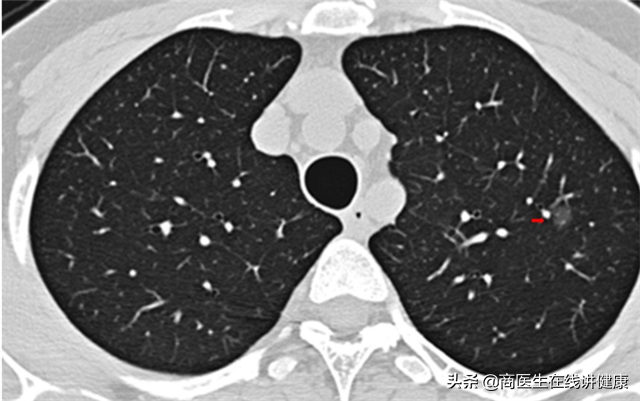

经过对患者叶女士询问后,我们首先推荐患者去做胸部CT。拿到CT结果后,发现患者果然在双肺多处均有结节状影像,存在多发性结节的情况。从CT上看,结节的大小和实性均不一。但从大小上看,都属于微小结节,且性质上也均属于毛玻璃状。

连续入院治疗十天后,患者叶女士咳嗽及咳痰等症状已明显缓解,随后再次做了肺部CT复查,CT检查结果显示,多个肺部结节已经通过治疗后消失,仅有右肺下叶处一个结节仍在影像结果中有显示,但对比入院的CT结果来看,此结节的影像也有所变淡,但大小并无明显变化。

就治疗结果来看,除了此处这一结节暂时不能确定其性质,其他多处结节已证实,均为炎症所致,入院治疗的效果非常好。